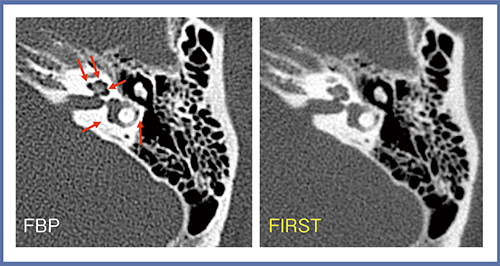

3.正常例の側頭骨

側頭骨についてFBPとFIRSTを比較すると,一見,FIRSTは鮮鋭さに欠けるように思えるが,FBPでは蝸牛や三半規管に小さな気泡のようなものが認められる(図5→)。図5は正常例で,実際には気泡状のものは存在しないと考えられることから,高吸収体に隣接して出現したアンダーシューティングであると判断でき,FIRSTの方が真実に近い画像であると考えられる。

図5 正常例:側頭骨